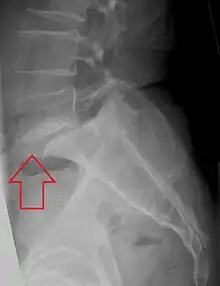

Normal lumbar vertebra showing large, round spinal canal

The normal lumbar central canal has a midsagittal diameter (front to back) greater than 13 mm, with an area of 1.45 cm2. Relative stenosis is said to exist when the anterior-posterior canal diameter measures between 10 and 13 mm. Absolute stenosis of the lumbar canal exists anatomically when the anterior-posterior measurement is 10 mm or less.[12][13][14]

Plain X-rays of the lumbar or cervical spine may or may not show spinal stenosis. The definitive diagnosis is established by either computerized tomography or magnetic resonance imaging (MRI) scanning. Identifying the presence of a narrowed canal makes the diagnosis of spinal stenosis.[15][16][17]